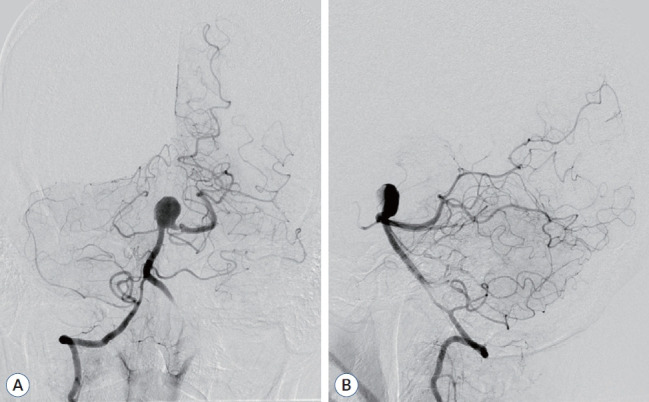

由于巨型部分血栓形成的颅内动脉瘤的自然病史并不乐观,而且缺乏标准化的治疗方法,因此治疗这类动脉瘤面临着巨大的挑战。传统的治疗方法,无论是开放手术还是血管内治疗,往往难以有效控制这些动脉瘤,导致高复发率或严重的发病率。患者是一名 62 岁的男性,基底动脉顶端有一个无症状的部分血栓形成的巨大动脉瘤,表现为左侧偏瘫和构音障碍。诊断成像显示该动脉瘤为巨型动脉瘤,宽颈、管状部分。为了最大限度地保障患者安全,患者接受了两阶段血管内治疗,包括球囊闭塞试验(BOT)和术中监测(IOM)。治疗采用了支架辅助编织内桥(WEB)栓塞和连续双侧椎动脉夹闭。手术成功分离了动脉瘤,术后成像证实没有再堵塞,保留了完整的后循环。患者在 12 个月的随访期间恢复稳定,未出现神经功能障碍。本技术报告展示了使用 WEB 装置和通过双侧椎动脉夹闭逆转血流治疗巨大的部分血栓动脉瘤的可行性和有效性。

Managing giant partially thrombosed intracranial aneurysms presents significant challenges due to their unfavorable natural history and the lack of standardized treatment approaches. Conventional treatments, whether open surgical or endovascular, often struggle to manage these aneurysms effectively, resulting in high recurrence rates or significant morbidity. The patient was a 62-year-old male with a symptomatic giant partially thrombosed aneurysm at the tip of the basilar artery, presenting with left-sided hemiparesis and dysarthria. Diagnostic imaging revealed a giant aneurysm with a wide-necked, canalized portion. A two-stage endovascular treatment was conducted, involving a balloon occlusion test and intraoperative monitoring for maximum patient safety. The treatment utilized stent-assisted Woven EndoBridge (WEB) embolization and serial bilateral vertebral artery trapping. The procedure successfully isolated the aneurysm and postoperative imaging confirmed the absence of recanalization, preserving the intact posterior circulation. The patient showed stable recovery and no neurological deficits during the 12-month follow-up period. This technical note demonstrates the feasibility and efficacy of strategically integrating intrasaccular flow diversion using a WEB device and flow reversal through bilateral vertebral artery trapping for treating giant partially thrombosed aneurysms.